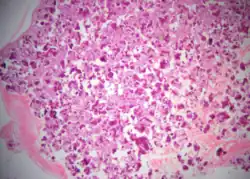

Histopathology

Cemento-ossifying fibroma is a well-demarcated lesion, often encapsulated by a thin fibrous capsule and sharply separated from adjacent normal bone. It shows significant internal variation, with differing amounts of fibrous and mineralized tissue—even within the same lesion. Mineralization is often more prominent centrally and typically includes osteoid, woven to lamellar bone, and dense basophilic cementum-like calcifications. Bony trabeculae may fuse into broad sheets or form thick, anastomosing strands. Osteoblastic rimming is commonly seen around bone trabeculae.[27]

The stroma is fibroblastic and may exhibit areas of hypercellularity and nuclear hyperchromasia; however, mitotic activity is rare and cellular atypia is minimal .[28] The mineralized component may include acellular or paucicellular cementum-like spheres along with bone structures .[28]

Though rare, hemorrhagic cystic degeneration—resembling aneurysmal bone cyst formation—can occur, more commonly in juvenile variants.[27][29] Histological overlap can exist among subtypes: psammomatoid and trabecular JOF may exhibit features resembling COF, and vice versa. In syndromic cases, such as gnathodiaphyseal dysplasia, COF lesions appear more fibrous with basophilic, acellular bone droplets and spherical ossicles, but histologically resemble nonsyndromic counterparts .[30]

Histologically, COF comprises a fibrocellular stroma with varying degrees of ossification, including trabecular or lamellar bone and cementum-like material.[35] Differentiation from other fibro-osseous lesions—such as fibrous dysplasia and cemento-ossifying fibroma—requires histopathological assessment.[36]